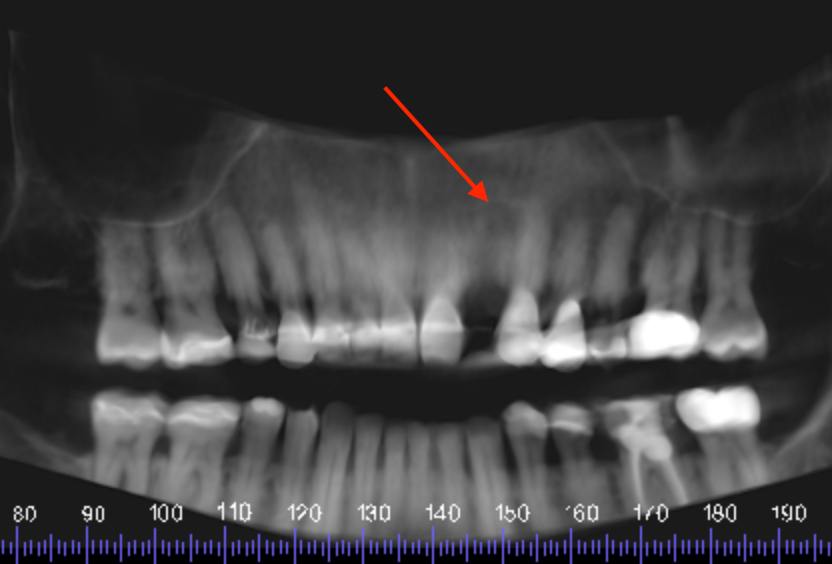

Post extraction CBCT reconstructed panoramic image showing circular radiolucency at edentulous UL2 apical region (red arrow).